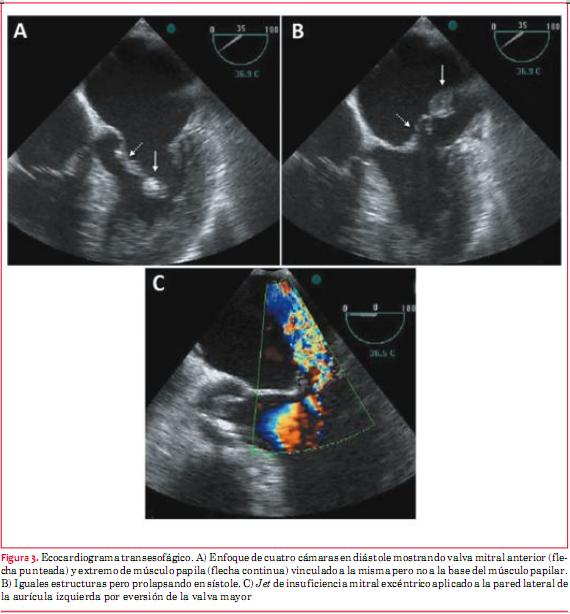

Paciente de 82 años de sexo masculino con antecedentes de tabaquismo e hipertensión arterial. Veinticuatro horas antes del ingreso presentó dolor retroesternal opresivo intenso durante un esfuerzo moderado, sin irradiaciones, acompañado de disnea, que calmó espontáneamente a los 15 minutos y por el cual no consultó. El día del ingreso reiteró nuevo episodio de dolor de iguales características pero de mayor intensidad, en reposo, acompañado de disnea y síndrome neurovegetativo, por el que consultó a las seis horas de iniciado el cuadro. Al ingreso se destacaba hipotensión arterial de 80/60 mmHg, estertores crepitantes en tercio inferior de ambos campos pulmonares y un soplo sistólico regurgitante en foco mitral de intensidad 2/6, irradiado a axila. Se realizó electrocardiograma en el que se comprobó infradesnivel del segmento ST de hasta 3 mm en DII, DIII y aVF y de V2 a V6 y supradesnivel del segmento ST de 1 mm en aVL (figura 1). Los marcadores cardíacos fueron positivos (CK total/MB 795/197 UI/l y troponina T 1,30 ng/ml). Se inició tratamiento antiisquémico con nitroglicerina i/v, persistiendo con ángor, siendo referido para cineangiocoronariografía de urgencia a las ocho horas de iniciado el segundo episodio de dolor. Esta se realizó por acceso radial derecho. Se comprobó que la arteria descendente anterior presentaba una lesión severa y extensa de tercio medio, el primer ramo diagonal una lesión severa proximal y oclusión proximal de uno de sus ramos de bifurcación, la arteria coronaria derecha una lesión moderada distal y el ramo descendente posterior una lesión crítica proximal (figuras 2 y 3). El procedimiento fue mal tolerado, con desaturación arterial de oxígeno por falla ventricular izquierda congestiva, extrasistolía ventricular frecuente e hipotensión arterial que requirió infusión de noradrenalina. Por este motivo y dado que el vaso culpable, probablemente el ramo de división ocluido del primer ramo diagonal, era un vaso de escaso desarrollo, se decidió no intentar una angioplastia coronaria. Se colocó balón de contrapulsación intraaórtico (BIAC). Por ecocardiograma (transtorácico y transesofágico) se comprobó rotura completa de músculo papilar anterior, insuficiencia mitral severa por eversión de la valva mayor de la mitral; función sistólica global conservada, sin alteraciones evidentes de la motilidad segmentaria (figura 4). El paciente evolucionó al shock cardiogénico refractario al tratamiento, falleciendo a las 12 horas de ingresado.

Colombo y colaboradores han demostrado que la sensibilidad del ETT y del ETE para la detección de la rotura del músculo papilar mejora significativamente con la medición, utilizando Doppler color, de la orientación del chorro excéntrico de la regurgitación mitral resultante. Al calcular el ángulo del chorro de la insuficiencia mitral proximal al plano del anillo, un ángulo £ 47° en ETE y ³ 45° en ETT presentaron una sensibilidad y especificidad de 88% para los flail de la valva mitral(7).